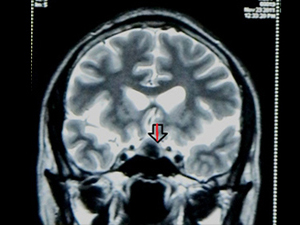

MRI PIC of a Pituitary Adenoma